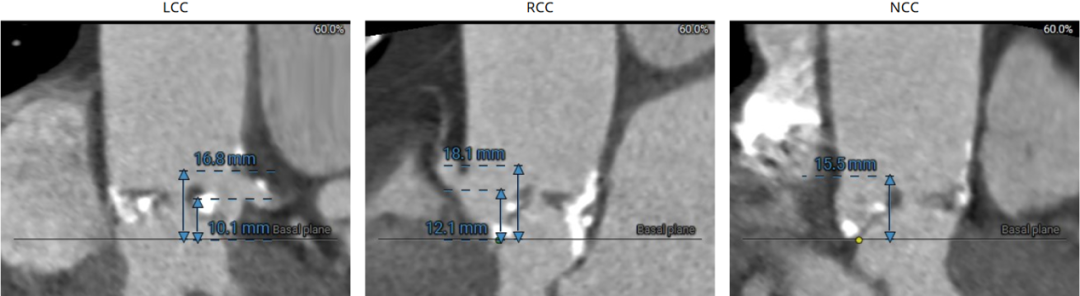

LCA 10.1mm,瓣叶长度16.8mm;RCA 12.1mm,瓣叶长度18.1mm:

左冠近端见钙化,STJ见钙化:

该患者瓣环最小径22.4mm,且瓣叶重度钙化,此外左无冠窦之间有一处柱状钙化延伸至LVOT,决定术中用20mm球囊预扩,评估冠脉风险和指导瓣膜选型。此外,患者双侧瓣叶长度均大于冠脉高度,且左冠团状钙化,冠脉遮挡高危,拟在TAVR前行左冠支架保护。